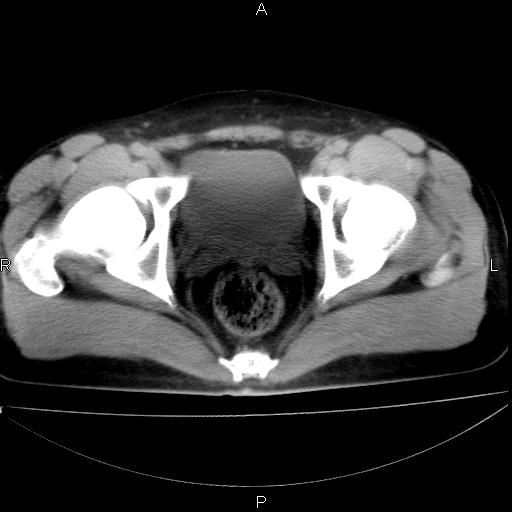

标题: CT29462:双测输尿管扩张

男 25岁 自述 尿频尿急,排尿困难20多天.无腰痛, b超说左肾盂轻度积水,左输尿管上端扩张.未见结石影. ct我看双侧肾盂轻度积水,双输尿管上端都扩张,大家看看能看见结石吗?

双肾盂及双输尿上段轻度积水,双输尿管未见明显结石影。

双肾盂及双输尿上段轻度积水

双肾轻度积水,双侧输尿管上段扩张(原因待查)。